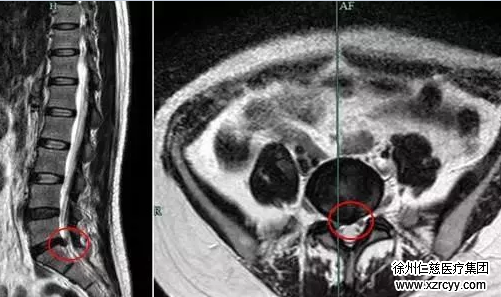

术前腰椎MRI显示可见L5/S1有突出,神经受到压迫(如红圈所示)

这是典型的微创内视镜手术的适应症,经过C臂机准确地透视定位成功置入工作通道并且顺利摘除突出物,术后患者立即感觉疼痛症状缓解。